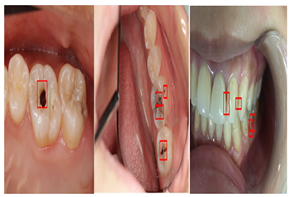

| Type | Publication Used | Variable Measured | Sample Image | Features |

|---|---|---|---|---|

| Ora Photographs | [50,51,58,89,128,129,130,131] | Gathered by consumer cameras | ![]() | They are easier and more cost-effective to capture. |

4.3.3. Oral Photographs

Oral images can be captured with the help of a consumer camera in a cost-effective and simple manner. It has become increasingly common for consumers to carry cameras, including smartphones, which are easy to use and have enhanced functionality [50,80].